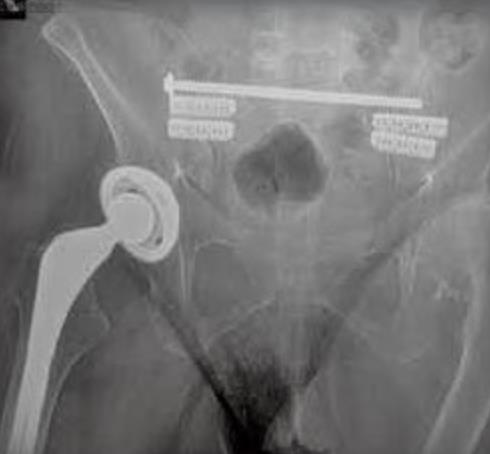

• iFuse-3D is a minimally invasive implant system intended to stabilize and fuse the sacroiliac joint by delivering triangular, porous, fenestrated titanium implants across the joint via a percutaneous approach.

• Minimally invasive lateral or oblique trajectory through a small incision with percutaneous instrumentation to place triangular implants across the SI joint.

• Plan trajectory under fluoroscopic guidance.

• Advance the guide pin with fluoroscopic confirmation of position and depth.

• Advance until seated; confirm final position with fluoroscopy.

• Place additional implants per preoperative plan.